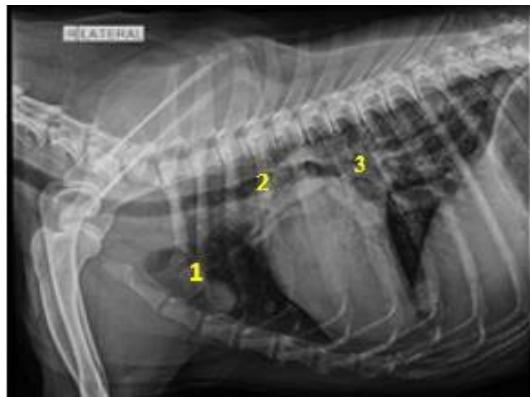

Fig. 5: Skiagram of the thorax on the right lateral view showing cranioventral mediastinal mass (1), tracheal displacement (2), and suspecting tracheobronchial lymphadenopathy (3) in dog A11